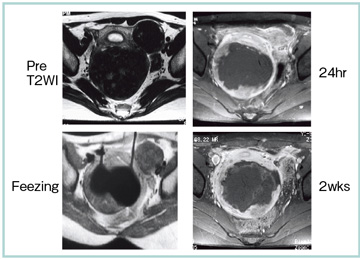

症例は,37歳,女性。凍結治療の24時間後と2週間後に造影MRIを撮像してみると,凍結領域と壊死に陥っている領域の形状とサイズがまったく異なっていた(図7)。その理由として唯一考えられるのは,筋腫内にある微小血管系が塞栓されたということである。つまり,子宮筋腫の治療においては,ある程度の領域を凍結すれば,症状の低減効果が得られると考えられる。また,粘膜下筋腫の治療6週間後の画像では,正常な信号強度の内膜junctional zoneおよび筋層が認められ,少なくともMRI画像上は凍結領域の痕跡は残っていない(図8)。つまり,凍結治療後も妊孕能が温存できる可能性があると考えられる。

図7 子宮筋腫症例(37歳,女性)